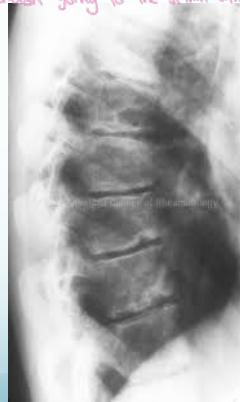

Radiographic Findings:

- Irregular ossification of vertebral body epiphysis

- Schmorl’s nodes -Central herniation of disc material into the body

- Wedging of vertebrae

X-ray Findings

- Schmorl’s nodes (central disc herniation)

- Vertebral wedging